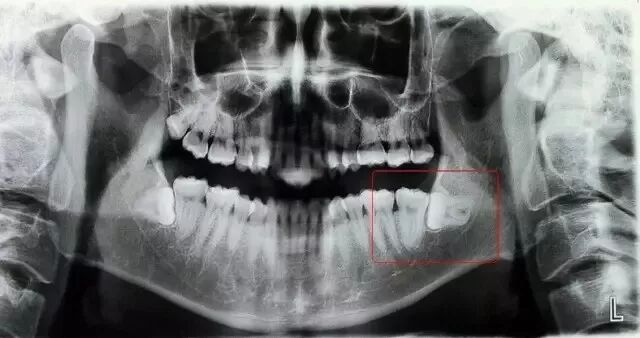

在X线片上可以看得很清晰。

智齿阻生时可呈垂直、前倾、水平、横向、倒置等不同方向萌出。当其部分萌出时,牙冠周围常被牙龈组织不同程度地覆盖,以致在牙冠与牙龈之间形成一个牙龈袋。